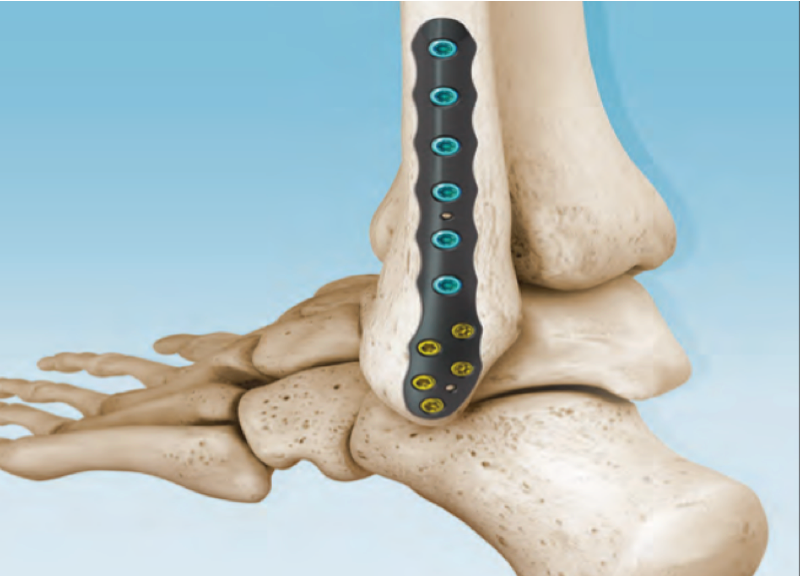

CONMED Foot and Ankle offers tailored innovation and simplified solutions. Explore our complete portfolio of arthroplasty, biologic, fixation, implant, suture anchor, and instrumentation offerings for foot and ankle surgery.

Dr. Early - First MTP Fusion Technique with Metatarsal Head Bone Loss